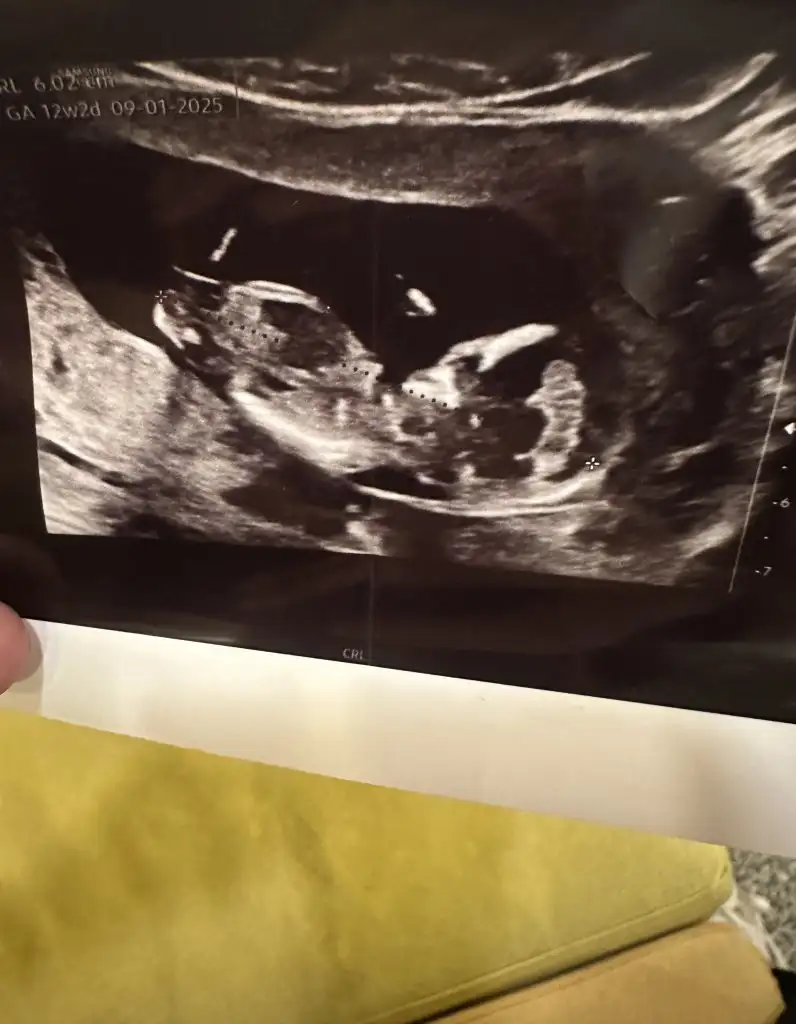

Yok be kuzum daha 10 haftalığız yarın kontrole gideceğim ama daha bi 3 hafta sonra anca belli olur tahminen bakalım yarınki ultrasonla az da olsa belki anlaşılırCinsiyet belli oldu mu kız

Doğuma girerken bana dua etcen bak unutma sakın kocana kaynana herkese söyle hatırlatsınlar sanaYok be kuzum daha 10 haftalığız yarın kontrole gideceğim ama daha bi 3 hafta sonra anca belli olur tahminen bakalım yarınki ultrasonla az da olsa belki anlaşılır![]()

Erkek demiştim dimi kız sana hatırlamıyorum koç gibi yatıyo işteCanım sana yeni resimle geldim![]()